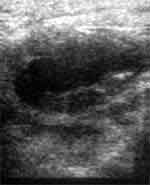

Рис. 1. Передняя брюшная стенка при продольном сканировании. Лоцируется участок пониженной эхогенности 11 мм в диаметре.

Рис 2. Правя подвздошная область. Абсцесс 25х22 мм.

Рис. 3. После дренирования полость абсцесса уменьшилась. Режим "увеличения".

У дистального края рубца на глубине 18 мм лоцируется уплотнение ткани 43х23 мм с гипоэхогенным участком в центре. Над лонным сочленением на глубине 11 мм лоцируется такой же участок 35х24 мм с эхонегативными очагами разряжения в центре. В правой паховой области с переходом на правое бедро на глубине 12 мм лоцируется эхонегативный участок с неровными нечеткими контурами 33х37 мм с взвешенными в нем мелкими экопозитивными образованиями. Кровотока в вышеуказанных патологических образованиях при ЦДК не определяется. Заключение: Абсцесс (флегмона) передней брюшной стенки, мышц правого бедра?